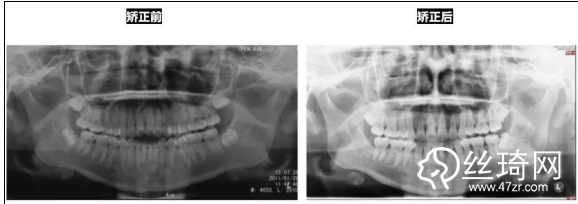

* 影像學(xué)檢查分析(以及調(diào)節(jié)前后影像對比):

全景片:

頭顱側(cè)位片:

前后頭影測量結(jié)果對比: